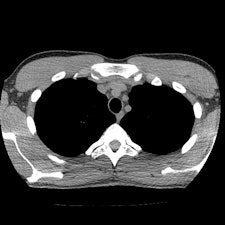

Anthropomorphic chest phantom for an adolescent. Direction-independent dosimeters were placed on each of the phantoms on several positions -- thyroid, upper and lower sternum, left and right anterior chest wall, bilateral on upper and lower lateral chest wall, as well as on the upper, middle lower spine.